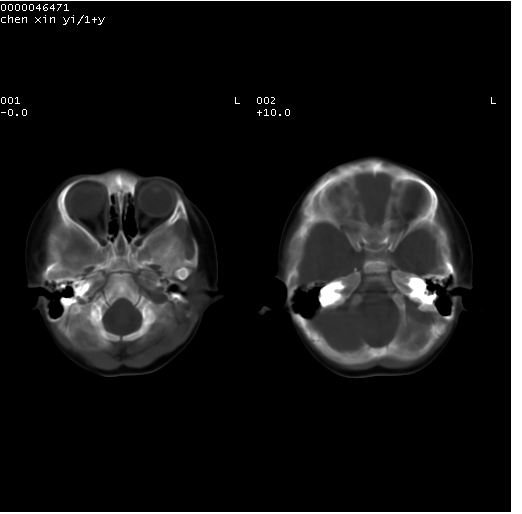

以下是引用zhangzhongshou在2008-4-9 12:54:00的发言:[br]请结合病史,有以下可能1、炎性肉芽肿钙化(含结核)2、寄生虫钙化(含脑囊虫)3、其他良性钙化性病变